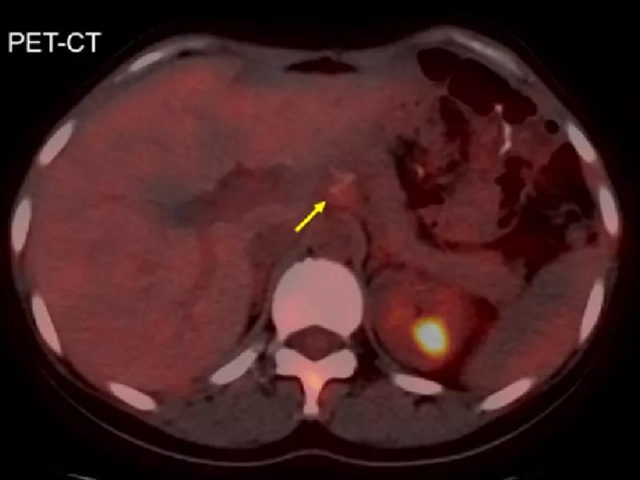

治疗前影像学评估肿瘤情况

(黄色箭头为转移淋巴结,红色箭头为肿瘤前方小动脉,绿色箭头为下腔静脉,蓝色箭头为腹主动脉)